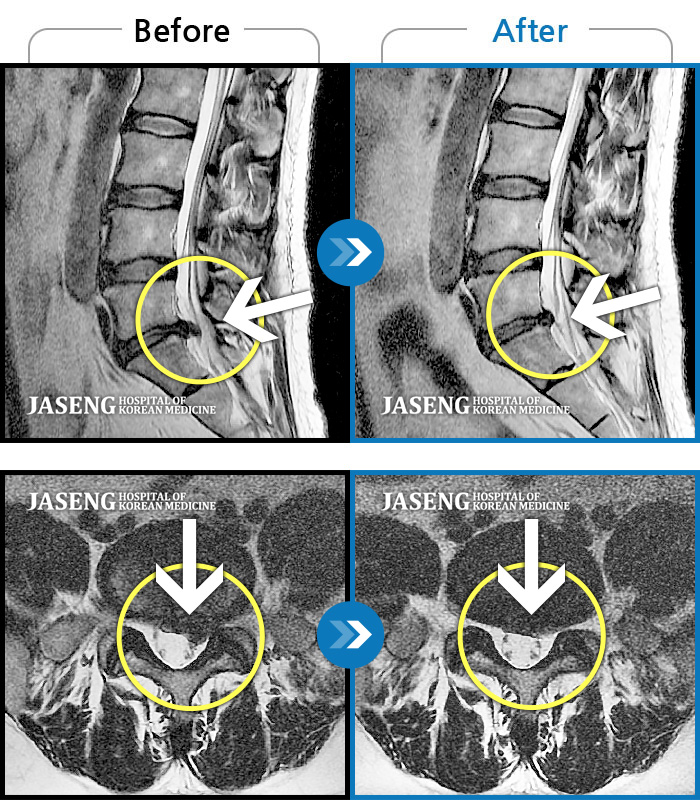

MRI 치료사례